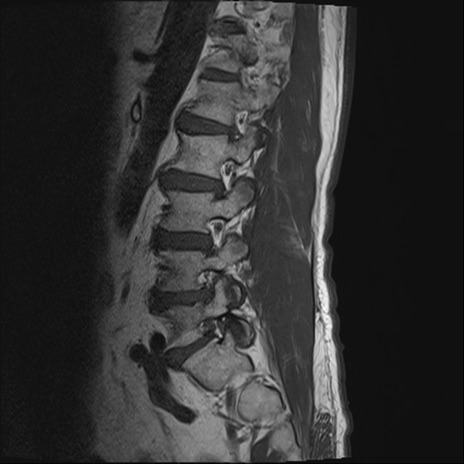

【整形】TIPS症例2 腰椎MRI T1WI(矢状断像)

【症例】70歳代男性

【主訴】左下肢痛

【現病歴】2週間前くらいから腰痛、左下肢痛あり。左臀部から大腿、下腿外側のしびれが常時ある。歩行とともに同部位の痛みあり。

【身体所見】Lasegue70-/60+、Bragard-/±、PTR ±/±、ATR -/-、IP 5/5、TA 5/4、TS 5/5、EHL 右第1足趾なし/3、FHL 5/5、hypersthesia(-)、足背動脈触知良好

異常所見と診断は?